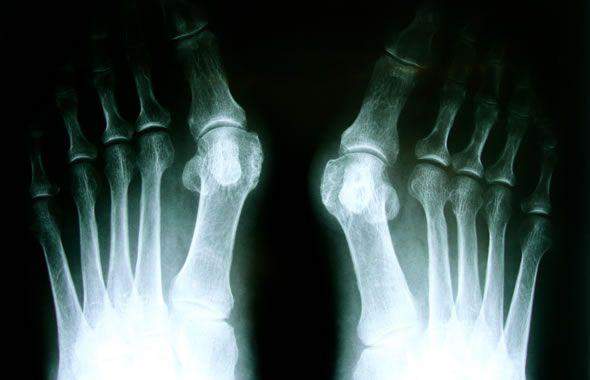

Che cos’è l’alluce valgo? L’alluce valgo è una deformazione patologica dell’articolazione metatarso-falangea, l’articolazione del primo dito del piede, l’alluce, il quale tende ad inclinarsi a ventaglio verso le altre dita portando visibilmente ad una deviazione laterale della struttura ossea del metatarso e alla comparsa di una sporgenza ossea tipica che, utilizzando una terminologia medica, viene definita un’ esostosi della testa metatarsale.

è sempre consigliabile chiedere il parere di un esperto, magari di un ortopedico che, dopo un’attenta visita durante la quale sarà stata stilata l’ipotesi diagnostica di un alluce valgo, vi chiederà senz’altro, per poterla confermare o meno, esami radiografici standard del piede sottocarico (in piedi) in proiezione antero-posteriore, laterale e con particolare dei sesamoidi, la cui lussazione è di regola la causa del dolore a carico di questa articolazione; esami di routine.